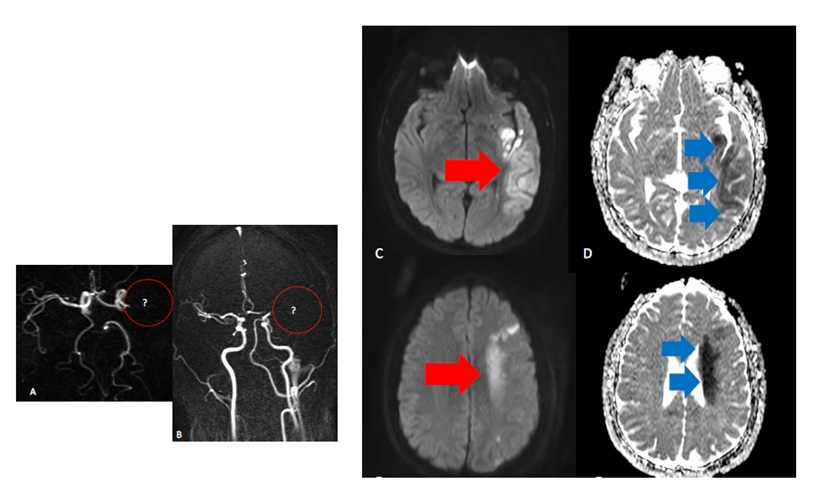

In addition, an increased risk of cerebrovascular events has been reported with SARS-CoV-2 infection and COVID-19, including hemorrhagic and ischemic strokes related to an increased risk of stasis and thrombocytic state of vessels.7 Case report series have reported an association between major occlusions of the arterial circle of Willis vessels and COVID-19, particularly in younger patients with catastrophic and malignant evolution as illustrated in Figure 1. Also given the complex thrombocytic pathogenesis of COVID-19-related abnormalities, this also refers to the lack of evidence-based standardization of treatments including stroke and other vascular lesions ensuring that treatments are not overshadowed by the pandemic.8,9 In the same time, there is a need for rethinking protocols of treatment as much endovascular treatment related to use of stents and other devices that are directly related to clot formation and change of blood rheology.

Figure 1 Left middle cerebral territory appearances in COVID -19 scenario . A, B occlusion of left MCA on the MRA (see red circles areas) C,D,E,F DWI shine and ADC abnormalities in the territory portions affected pointed by red and blue arrows.

Cerebral vascular diseases include a variety of medical conditions that affect blood vessels in the brain and hemostasis of the circulation. These disorders usually damage or deform the arteries that supply oxygen and nutrients for brain damage. Ischemic insult, or sometimes a hemorrhagic stroke usually caused by a temporary or permanent reduction in cerebral blood flow clinically manifested by occlusions (Figure 1), is a major cause of mortality and disability in the world. Various pathophysiological conditions, such as hypertension, atherosclerosis and prothrombotic states have been found to increase the risk of ischemic stroke. In addition, high levels of oxidative stress and inflammatory response in the brain in the early stages of ischemic stroke also contribute to irreversible brain damage after the ischemic insult.27–29